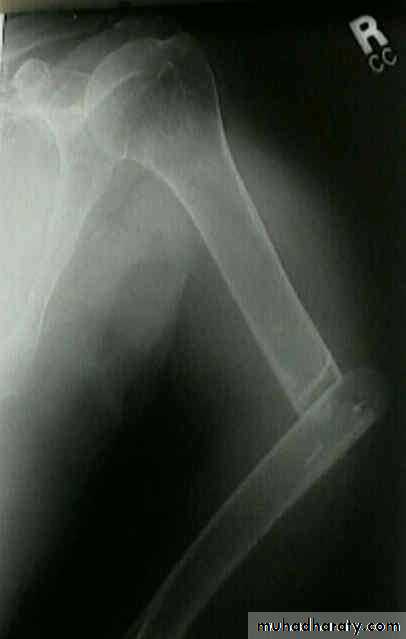

Upper limb

Fall on out stretched hand

40 years male fall on out streched hand

Radial nerve palsy after reduction